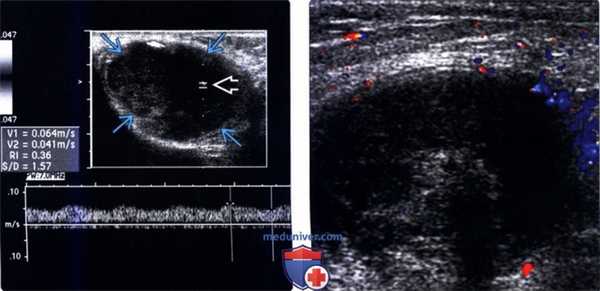

2. УЗИ при неопущении яичка:

• В-режим УЗИ:

о Отсутствие яичка/семенного канатика внутри мошонки

о Гомогенное гипоэхогенное образование овальной формы с четкими контурами, размером меньше нормального опустившегося яичка:

- Для того чтобы с помощью УЗИ отличить неопущение яичка от прочих образований паховой области, следует идентифицировать эхогенную линию средостения яичка

- Отсутствие скопления жидкости вокруг яичка и его сдавливание со стороны окружающих структур делает края неопустившегося яичка менее четкими, чем у нормально расположенных яичек

- Яичко размером менее 1 см не выявляется

о Неопущение яичка у взрослых проявляется разной степени атрофией с измененной эхогенностью паренхимы

о Ассоциация с микролитиазом; очаги неоплазии также могут быть выявлены в случае их наличия

(Справа) УЗИ, В-режим: визуализируется неопущение яичка с многочисленными (более пяти в поле зрения) точен ными гиперэхогенными очагами без акустического затенения, что соответствует микролитиазу. Наличие микролитиаза в неопустившемся яичке ассоциировано с повышенным риском развития рака яичка. Данный пациент требует постоянного наблюдения.

(Слева) Спектральная допплерография неопусгившегося яичка: внутри яичка определяется гипоэхогенное образование с внутренним кровотоком. Патоморфологическое исследование подтвердило, что данное образование является семиномой.

(Справа) Цветовая допплерография: визуализируется неопущенное яичко. Гетерогенная эхогенность и отсутствие цветовой визуализации потока внутри указанного яичка указывает на перекрут яичка.